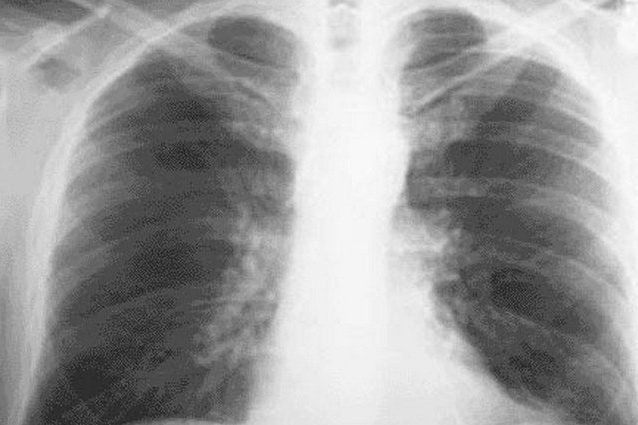

Un team di ricerca della Città della Salute e della Scienza di Torino - Ospedale Molinette ha dimostrato che attraverso un'ecografia ai polmoni (accompagnata da una visita medica) è possibile diagnosticare prima del tampone oro-rinofaringeo i casi di COVID-19 con polmonite. Test su 140 pazienti ha rilevato il 20 percento di positivi, risultati tutti negativi al primo tampone.